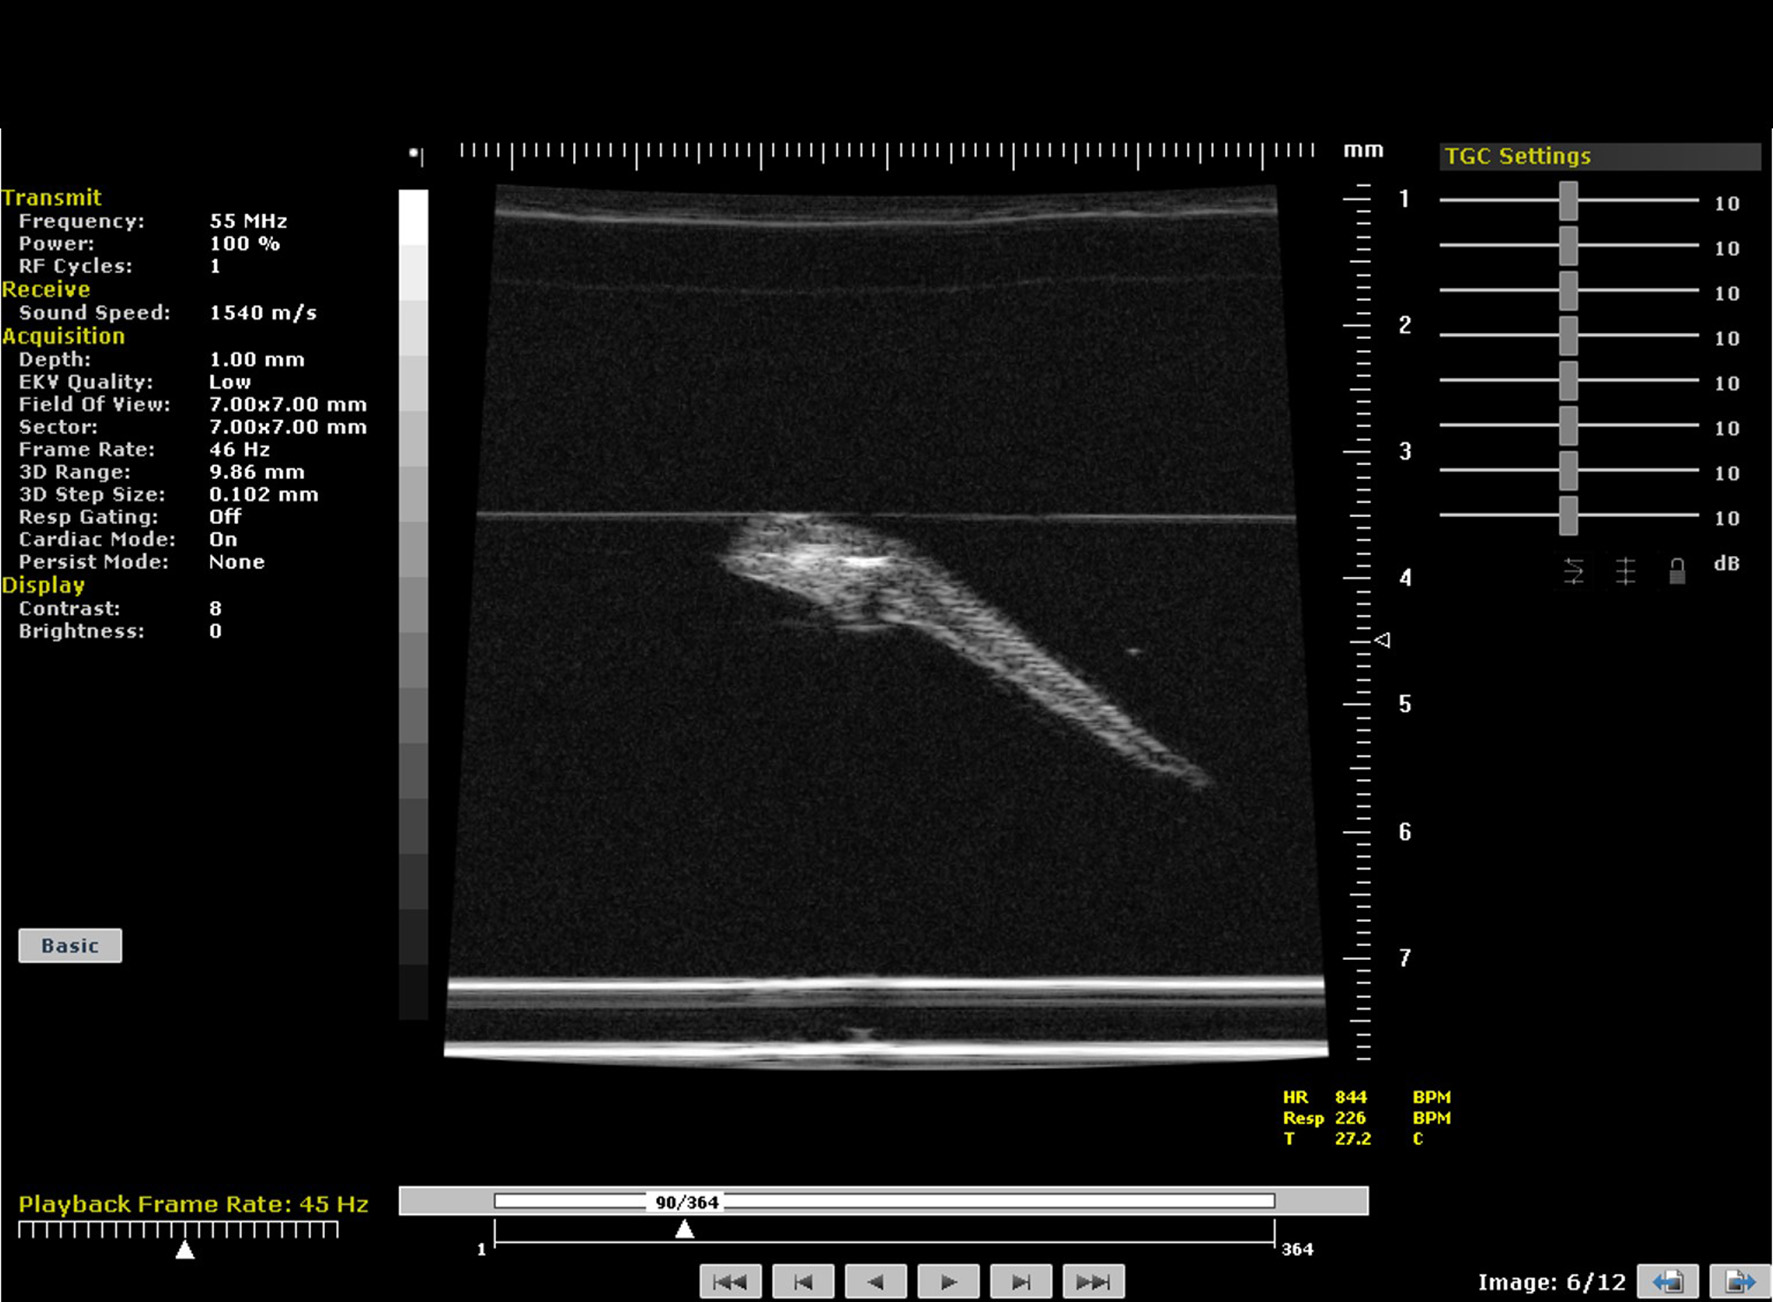

The cardiac function of zebrafish can be imaged using preclinical ultrasound. The zebrafish heart is composed of 4 chambers—sinus venosus, atrium, ventricle and bulbus arteriosus. Light anesthesia can be induced for adult fish by injection of MS222 in the tank water. The fish can then be manipulated and placed on their dorsal side and gently restrained using plasticine that is lightly hand-molded around their bodies. Transducers up to 55 MHz can be used to image the hearts in both long and short axis views. Obtaining an ECG signal from adult zebrafish is challenging so the timing of systole and diastole is determined from cardiac chamber size and spectral Doppler traces with adult heart rates ranging from 120 to 180 beats/min. Additionally, the echogenicity of blood within adult zebrafish is similar to the surrounding tissue structures (Figure 12) making the differentiation of chamber volumes challenging.

FIGURE 12

www.frontiersin.org

Figure 12. Spectral and color Doppler (Duplex) image of adult zebrafish heart.

Measurement of Cardiac Function in Embryonic Zebrafish